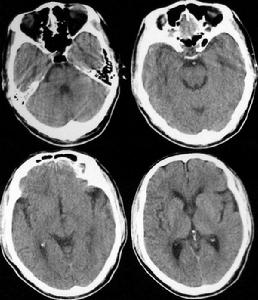

頭部病變即腦部病變,一般就是在腦部影像學檢查中發現了異常部位,其異常部位的大小大概有拇指大小或者更大。腦部的異常病變多見於腫瘤,出血,鈣化,梗塞等情況,頭痛是頭部病變最常見的症狀之一。